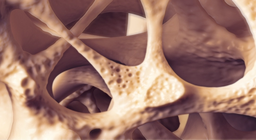

Osteoporosis is a disease of progressive bone loss, it is called a “silent" disease because there are typically no symptoms until a bone is broken.

Osteoarthritis encompasses a range of joint diseases with being the most common degenerative type.